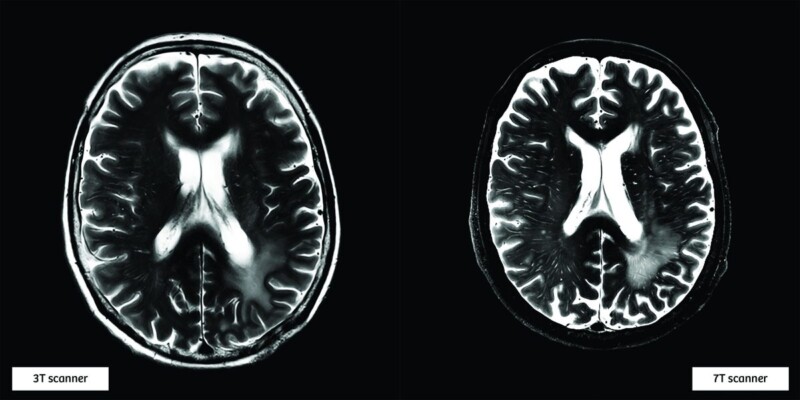

The 7 tesla (T) MRI scanner Magnetom Terra, made by Siemens Healthineers, operates with a very strong 7T magnet, whereas most MRI scanners operate with 1.5T or 3T magnets. The higher magnetic field results in more detailed, higher quality images which can detect the more subtle changes diseases cause in the body.